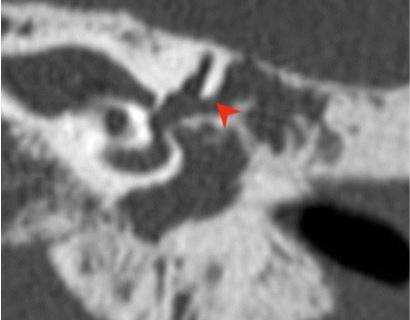

Один пациент, по данным КТ височных костей, имел двустороннюю облитерацию лабиринта, включая улитки с двух сторон, с большей выраженностью патологических изменений справа. На МРТ было выявлено уменьшение количества жидкости в улитке справа, слева количество жидкости в улитке соответствовало норме (рис. 1, 2).

Рис. 1. КТ, аксиальная проекция. Облитерация улитки (стрелка).